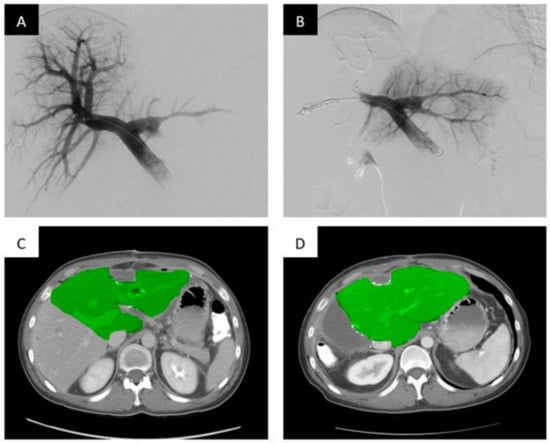

Another liquid embolic/sclerosing agent which has been gaining favor recently has been sodium tetradecyl sulfate (STS) foam. Its low cost and ease of use has become a factor in its adoption. The liquid sclerosant is turned into a foam by the mixture of air and oil-based contrast agent (lipiodol), which allows full contact with the vascular endothelium when injected into the venous system. Theoretically, foam allows for higher surface area contact and makes it a better embolic agent than liquid agents. The agent itself results in inflammation and subsequent thrombosis/sclerosis upon contact with vascular endothelium [40,41] (Figure 3).

Portal vein embolization of the right portal vein branch with STS foam demonstrates FLR hypertrophy. Portal vein embolization (PVE) of the right hepatic portal vein with STS foam. (A) Digital subtraction portography prior to embolization via access of a peripheral right anterior division portal vein branch. (B) Post-embolization single shot image of the right portal system opacified with lipiodol-stained STS foam. A 7 F Fogarty balloon (Edwards Lifesciences, Irvine, CA) is used to occlude the proximal right portal vein and maintain patency from the main portal vein to the left portal vein (black arrow). (C) Axial contrast-enhanced computed tomography (CT) slice demonstrating the pre-embolized liver, with the non-hypertrophied left lobe highlighted. (D) Post-PVE contrast-enhanced axial CT slice demonstrating noticeable hypertrophy of the left liver post-right PVE and hepatectomy (approximately 21 days post embolization).

In a single-center retrospective review, Fischman et al. described successful PVE and FLR growth in 35 patients with STS foam [42]. Adequate FLR hypertrophy was achieved in 31 of the 35 patients (88.6%) at 30 days. The mean percentage increase in FLR was observed at 11.9% ± 10.2. Importantly, the authors described absolute and percentage FLR increases that did not significantly differ based on type of underlying liver function (healthy, steatosis, chemotherapy, cirrhosis). Fever and post-embolization syndrome were reported in 10 of the 35 patients (28.6%) a much larger cohort compared to other embolic agents. A total of 27 of the 35 patients (77.1%) underwent surgical resection, with no reported 30-day fatalities.